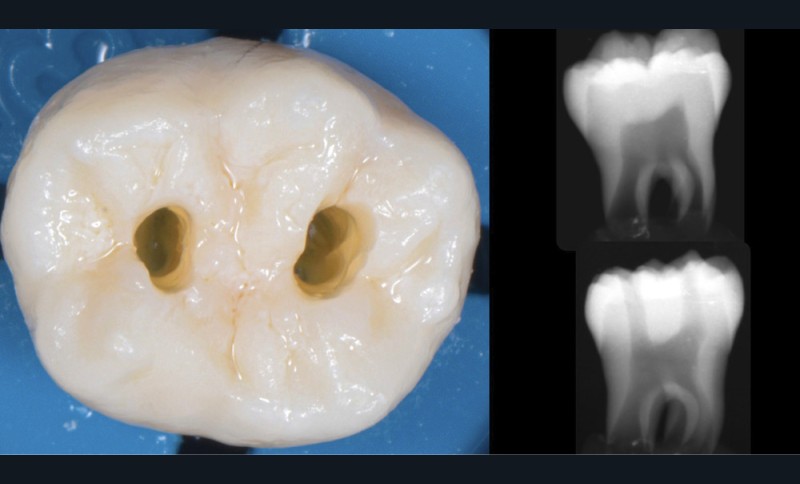

Une cavité d’accès trop petite [2] optimiserait le pronostic biomécanique (préservation dentaire maximale) mais pourrait compromettre le pronostic endodontique : mauvaise lecture de l’anatomie, instrumentation partielle, non ergonomique et avec risque de fracture, défaut de nettoyage des parois canalaires [3], irrigation inadéquate, difficulté d’obturation canalaire, voire d’obturation coronaire. Ce sera le cas des cavités d’accès « Ninja » [4] ou ultraconservatrice (fig. 1), des cavités d’accès « Truss » [5] (fig. 2), des cavités d’accès dites « opportunistes » [6] (fig. 3).